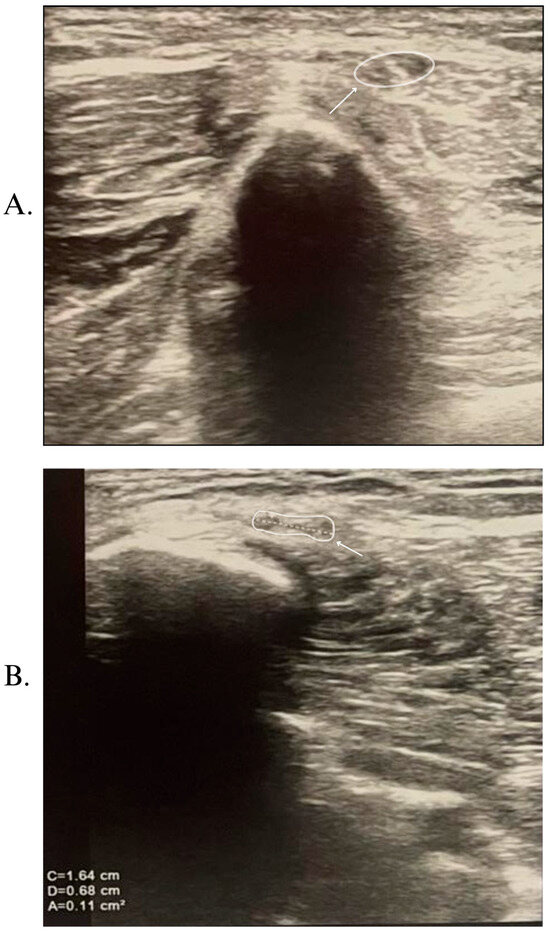

2. Case Report

- Meylaerts, L.; Cardinaels, E.; Vandevenne, J.; Velghe, B.; Gelin, G.; Vanormelingen, L.; Weyns, F. Peroneal neuropathy after weight loss: A high-resolution ultrasonographic characterization of the common peroneal nerve. Skelet. Radiol. 2011, 40, 1557–1562. [Google Scholar] [CrossRef]